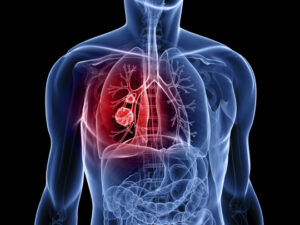

Химиотерапия при раке легкого — один из основных способов разрушающего воздействия на опухоли данной локализации. В зависимости от стадии и распространенности онкозаболевания этот метод может применяться как изолированно, так и в комбинации с оперативным и лучевым лечением. Эффективность применения химиотерапии зависит от

чувствительности злокачественных клеток к выбранным препаратам, переносимости лечения самим пациентом и стадии процесса. Значительно улучшает прогноз при раке легкого ранняя диагностика и быстрое начало лечения после постановки диагноза.

Особенности химиотерапии при раке легкого

- размер и локализация первичного очага;

Вероятность позитивного исхода при раннем обнаружении и своевременном начале лечения довольно высока.